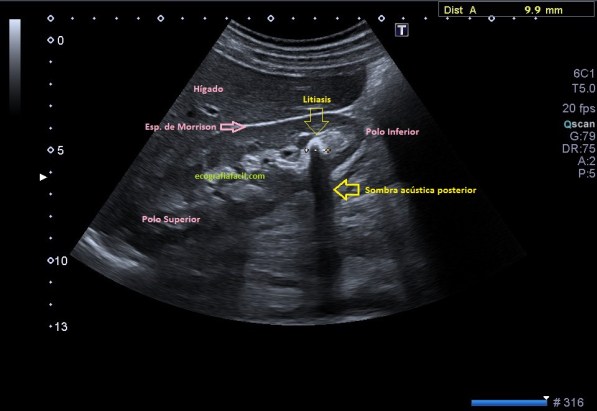

Al realizar la ecografía consigo demostrar una litiasis muy ecogénica con una potente sombra acústica posterior en el polo inferior del riñón derecho. En la petición del especialista se especificaba control de litiasis bilateral, sin embargo, en el otro riñón no había ni resto de litiasis. Pregunté a la paciente si había tenido cólicos nefríticos expulsivos (con expulsión de piedra) desde el último control, su respuesta fue negativa. Dado que tenía controles previos, los consulté, en la última eco realizada, 8 meses atrás no había piedras en el riñón izquierdo, donde yo no había visto en la actualidad, pero ví que entre una y otra ecografía había un TC de Abdomen sin contraste. En el TC se observaban litiasis renales milimétricas, varias, en el seno renal izquierdo, invisibles en la ecografía.

La secuencia de imágenes que has visto es el proceso que ha llevado la paciente, con una ecografía antes del TC con el mismo resultado en cuanto a litiasis que la última que corresponde con las imágenes 6, 7 y 8 donde puedes ver la litiasis renal derecha grande, en el grupo calicial inferior en longitudinal y en transverso. Riñón izquierdo rigurosamente normal, por más que pude buscar, aún a sabiendas de que en el TC habían salido piedras en ese riñón, además, agrupadas en los diferentes grupos caliciales, imágenes 2 y 5, en las reconstrucciones coronales como en los cortes axiales, pero llama poderosamente la atención como junto a la litiasis del RD en el TC, imagen 3, se ven otras dos pequeñas litiasis, imagen 4, que tampoco pude objetivar en la ecografía, ni se vieron en la ecografía anterior. La Rx señala la vista en las ecografías.